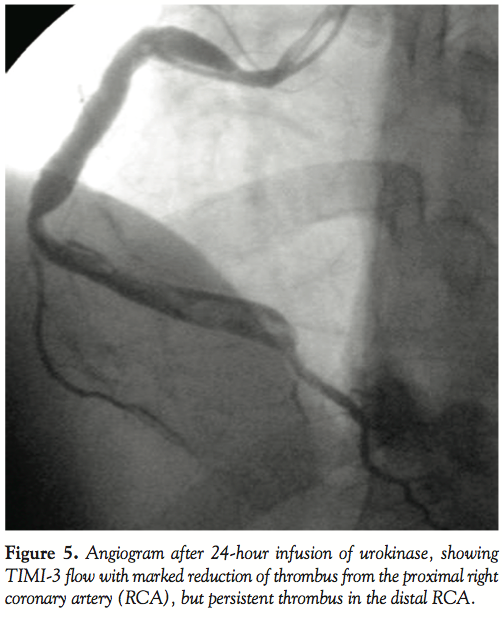

maneuvered up to the distal RCA (Figure 3). Manual suction of thrombus was then tried by attaching it to an airtight, 20 ml luer-lock syringe and gradually withdrawing it from the distal to proximal RCA. Maintaining negative suction, the guiding catheter was slowly withdrawn from the RCA and the femoral sheath. Flushing the guiding catheter outside revealed small pieces of thrombi. Angiogram following this maneuver showed appreciable reduction of the thrombus burden in the proximal RCA, but the distal RCA was still loaded with thrombus (Figure 4). The same maneuver of advancing the guiding catheter over a guidewire and Tracker catheter into the distal RCA and aspiration of thrombus was repeated. However, external flushing of the guiding catheter did not reveal any thrombi and repeat angiogram was identical to that obtained after the first aspiration. As TIMI-2 flow was achieved, we thought of tackling the residual thrombus by pharmacological means. Infusion of abciximab was continued for 12 hours. Infusion of unfractionated heparin (1,000 U/hour) was continued for 24 hours. The patient was kept under invasive hemodynamic monitoring in the coronary care unit. A check angiogram at the end of 24 hours revealed TIMI-3 flow with marked reduction of the thrombus burden in the proximal RCA and persistent large thrombus in the distal portion (Figure 5).

As there was normal antegrade flow with a residual thrombus burden in the ectatic distal RCA, the patient was put on oral anticoagulants maintaining an INR of around 2.5 (to prevent further thrombus formation), which was overlapped with intravenous heparin infusion (keeping the activated partial thromboplastin time > 50 seconds) with the hope that the endogenous fibrinolytic system would eventually dissolve the residual thrombus. The patient was kept under close clinical follow up. Though the patient was clinically asymptomatic, an angiogram at the end of the 9 months revealed the ectatic RCA with TIMI-3 flow and no evidence of thrombus (Figure 6).